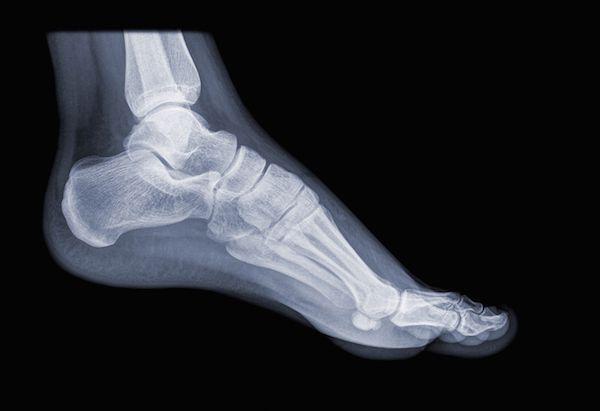

- Stress Fractures: Particularly in the metatarsals, as barefoot running increases load on the forefoot.

- Achilles Tendinitis: Caused by the additional strain on the Achilles tendon due to the absence of a raised heel.